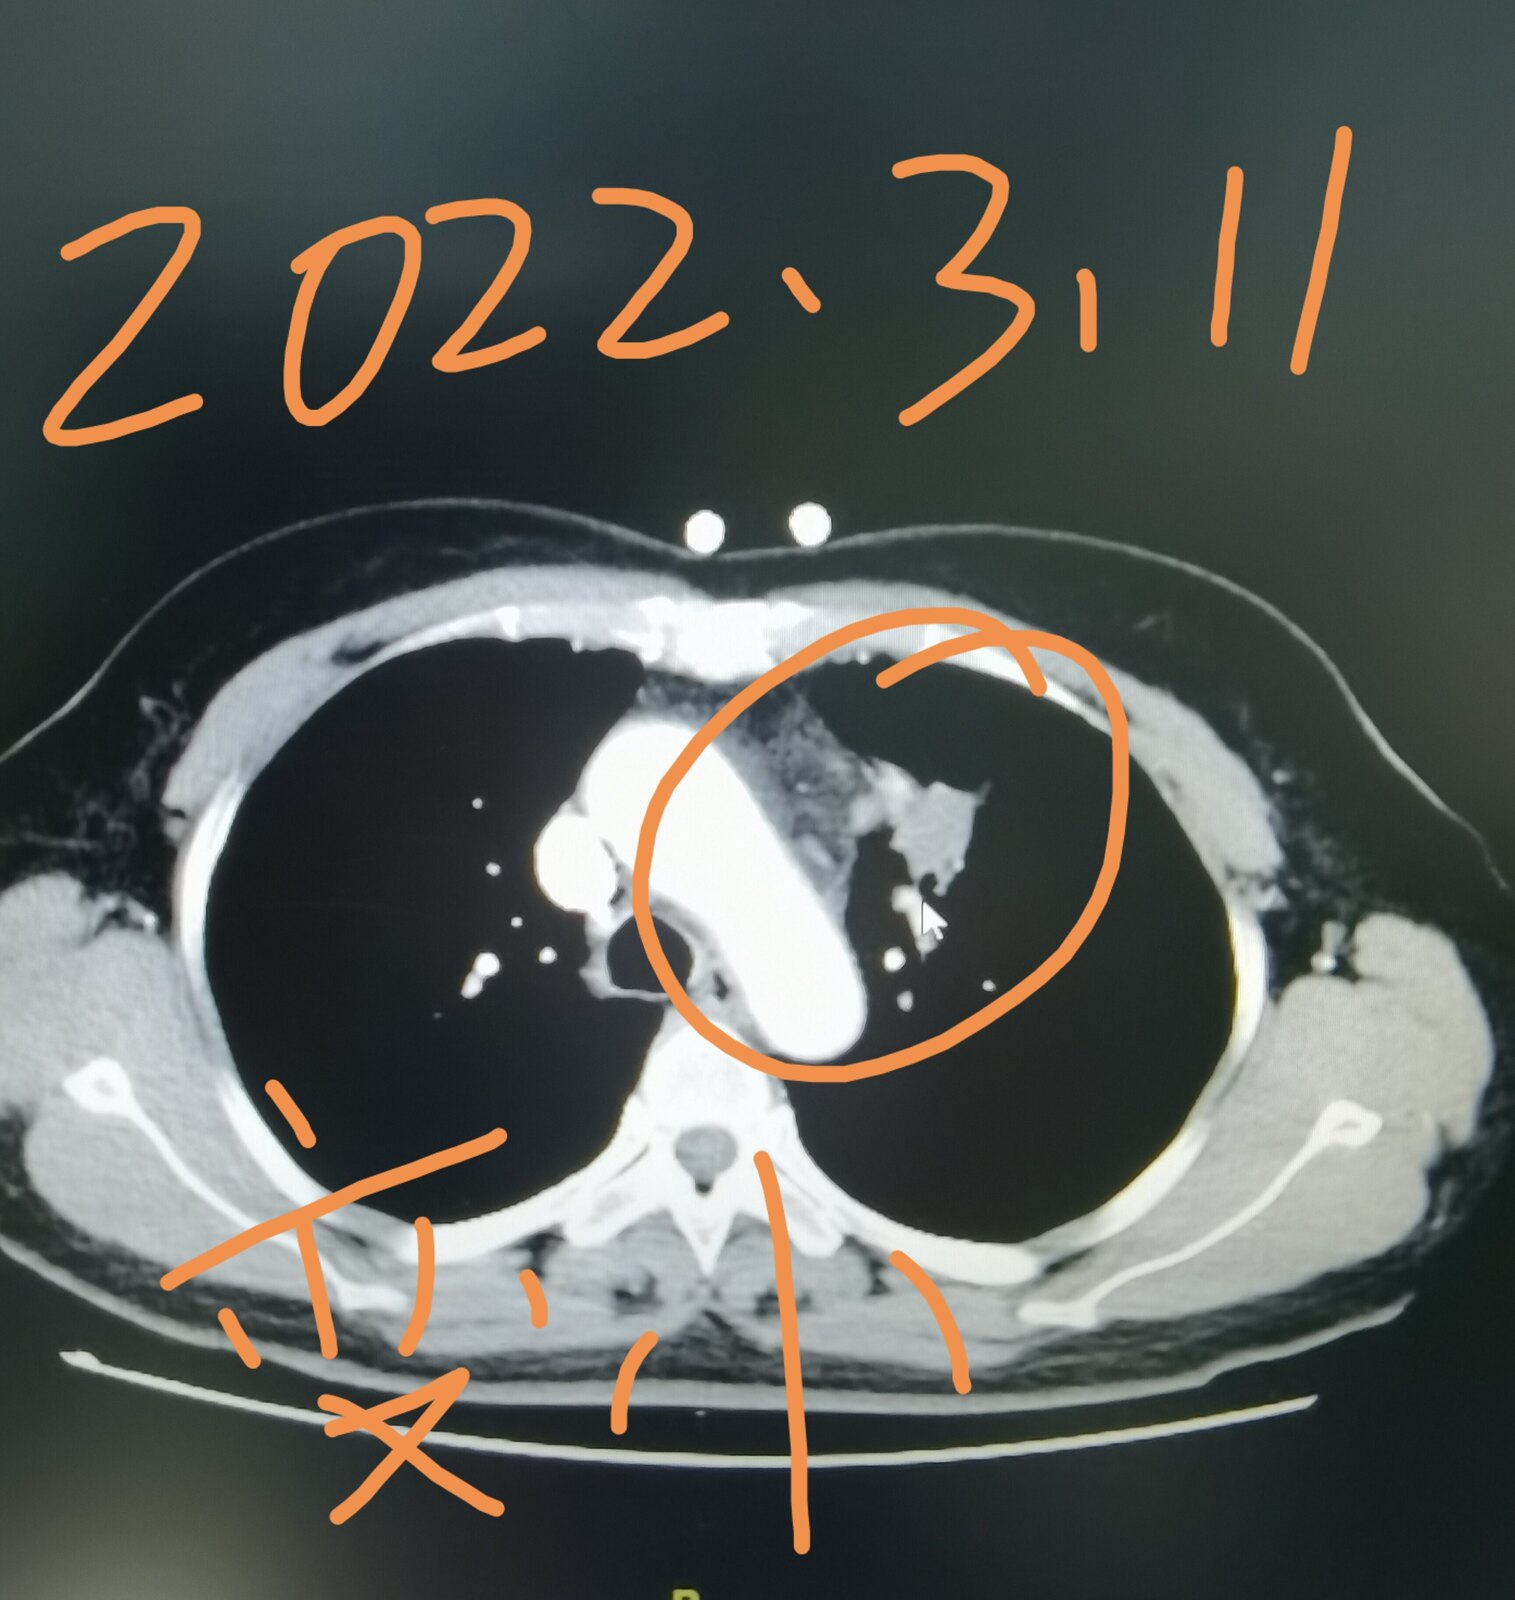

今天有一台手术就属于这个情况,我把这位患者的片子给大家发在下面,这是一位51岁的女士,三个月前因为咳嗽在当地医院拍片子,发现了肺部占位,她过来找我,想在我这里治疗。我给她进行了系统的检查,当时发现左上肺这个占位侵犯了纵隔,纵隔淋巴结增大,考虑转移,直接手术效果不好。这位女士好在其他部位并没有转移,我给她安排了穿刺,病理显示是一个肺腺癌,做基因检测,存在EGFR敏感突变,她吃了两个月的靶向药,肿瘤和淋巴结都缩小了。今天给她做的手术,手术过程是很困难的,里边粘连的比较严重,血管也很难分离,但过程很顺利,现在正在密切观察中。她除了左上肺这个病变之外,左下肺还有一个结节,吃靶向药也没有减小,术中探查的时候,考虑是一个肺内淋巴结,也给她一并切了下来。

通过这个病例我们知道,有些局部晚期肺癌,通过吃靶向药使肿瘤缩小,仍然有手术机会,并且效果会更好。